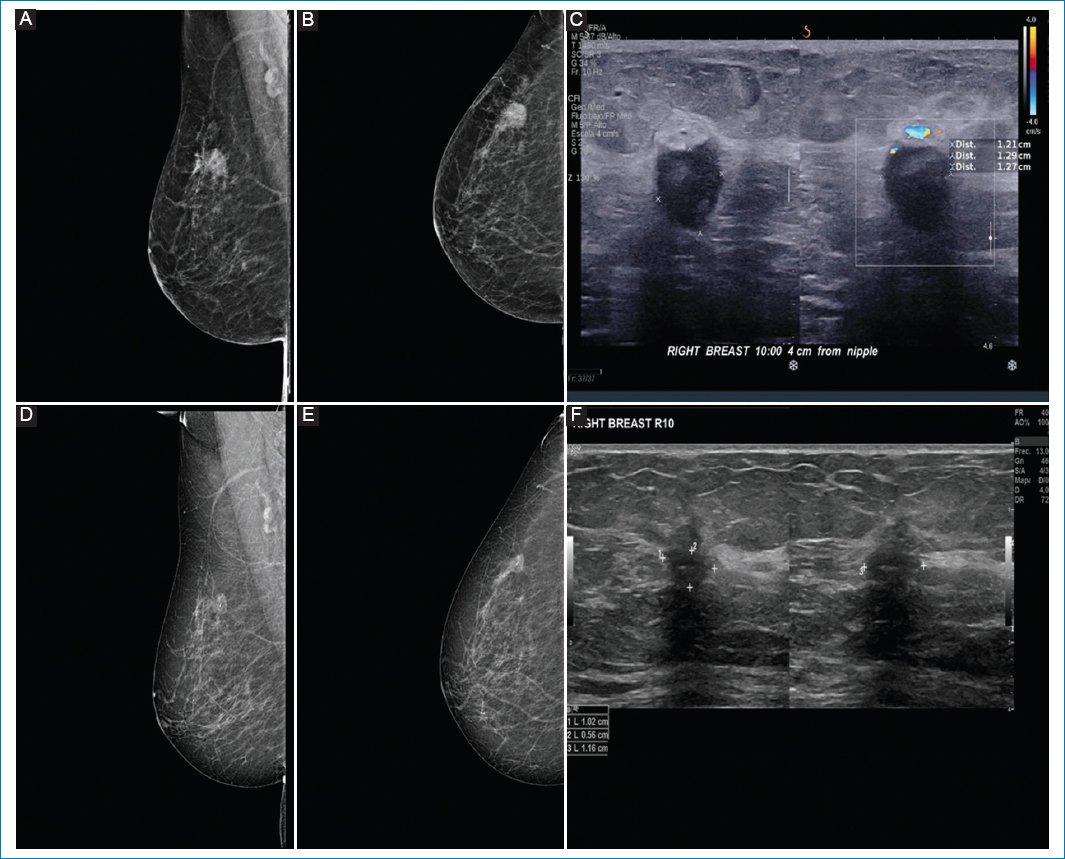

Pathologic response by imaging was classified as partial in 55.8% of cases (Figs. 1 and 2), complete in 34.6% (Figs. 3 and 4), stable (Fig. 5), or progressive disease in 9.6%. By pathology (RCB), response was complete in 53.8%, partial in 34.6%, and progressive in 11.5% (Fig. 6).

Figure 2. A-C: pre-neoadjuvant images. D-F: post-neoadjuvant images. 64-year-old patient with diagnosis of infiltrating ductal carcinoma of the right breast, clinical stage IIB, triple negative. A and B: pre-neoadjuvant mastography specimen with irregular nodule in upper outer quadrant. C: ultrasound specimen with irregular nodule in R10. D and E: correspond to the mastography. F: ultrasound showing a nodule with partial response to treatment and the presence of intratumoral clip.